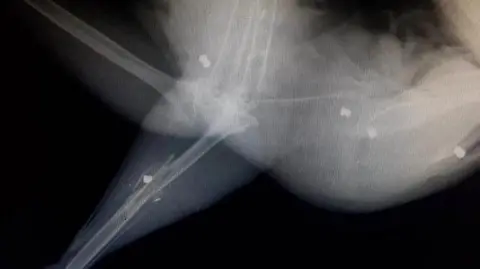

The bird was put down after he was shot six times with an airgun according to People for the Ethical Treatment of Animals (PETA), which is offering the reward.

The peacock was found in a field in Hinstock near Market Drayton, Shropshire, in January with pellets lodged in his body.

The animal’s injuries included a shattered leg and severely damaged muscles and tendons.

Centre manager Lee Stewart said: "From the amount of pellets we found, it's clear that someone has set out to intentionally kill this peacock rather than taking a quick pot-shot and unfortunately they succeeded."